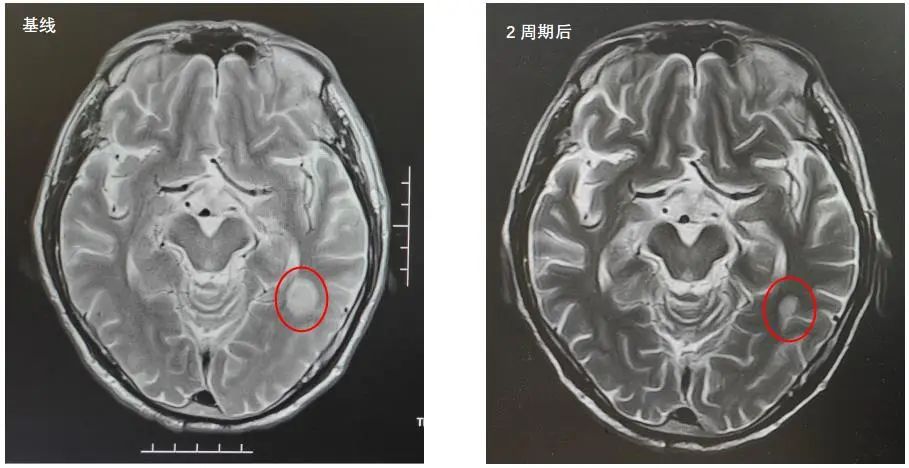

2022年5月9日MRI结果:左侧颞叶强化灶,考虑转移瘤。

2022年7月5日复查脑部MRI提示:与PACS20220529老片对比,现片示:左侧颞叶强化灶较前稍缩小。

总体疗效评价为PR。

MRI:与PACS20220529老片对比,现片示:左侧颞叶强化灶较前稍缩小。

疗效维持PR。

该患者是一个基线伴有脑转移的广泛期小细胞肺癌患者,《2022年CSCO小细胞肺癌诊疗指南》推荐,对于无症状的脑转移小细胞肺癌患者,一线治疗推荐免疫联合化疗后,再行全脑放疗。此患者在进行4个周期斯鲁利单抗联合卡铂依托泊苷治疗后,影像学提示病灶明显退缩,脑转移病灶也明显缩小,疗效达到PR,充分证明斯鲁利单抗在广泛期小细胞肺癌患者中的良好疗效。